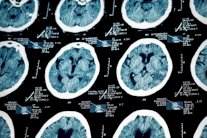

إيلاف من برلين: كان علماء البيئة يحسبون الخطر الذي تمثله عوادم السيارات على البيئة بحساب عدد الذرات المضرة التي تنطلق منها، لكن البحوث الأخيرة في العقدين الماضيين أثبتت أن الخطر ينجم عن ذرات صغيرة من السخام تخترق الحاجز المناعي في الرئتين وتستقر في أنسجة الجهاز التنفسي. وتقول دراسة حديثة أجريت على أدمغة بشر ماتوا في مدينتين ملوثتين إن ذرات السخام الصغيرة قادرة أيضًا على اختراق الحاجز الدماغي، والاستقرار في الخلايا الدماغية، والتطور إلى ذرات ممغنطة تسحب البروتينات وتراكمها حولها.

في مقالة نشرها علماء في مجلة Proceedings of the National Academy of Sciences قالوا إن جزيئات المعادن النانوية في ذرات السخام المنطلقة من عوادم السيارات تستقر في الدماغ، وربما تسبب الخرف (الزهايمر) وأمراضًا دماغية أخرى.&

وتحدثت الباحثة بربرا ماهر وزملاؤها من جامعة لانكستر عن أضرار دماغية تم رصدها في أدمغة 37 إنسانًا عاشوا في مدينتي مكسيكو ومانشستر وماتوا فيهما. وقد عثر الباحثون في عينات من هذه الأدمغة على جزيئات أوكسيد الحديد الممغنطة التي يعتقد انها المسبب الأساس للأضرار الدماغية.

أضاف هؤلاء الباحثون أن الكشف عن مغنطة ما بين خلايا الدماغ مهم جدًا، فالبحوث السابقة برهنت على وجود علاقة بين الزهايمر وهذه المغنطة الدماغية، ومن المحتمل أن تجذب هذه الجزيئات المعدنية الممغنطة جزيئات "بيتا أميلويد" وتراكمها في خلايا الدماغ. وبيتا أميلويد هي المادة المتهمة بالتسبب بمرض الزهايمر وبتفاقمه لاحقًا، وبالأضرار الدماغية الناجمة عنه في المصابين بالمرض.

تكوّن البلوريات المعدنية في الدماغ أمر معروف طبيًا منذ زمن بعيد، بحسب ماهر وزملائها، لكن الأضرار التي رصدت في أدمغة 37 شخصًا المذكورين أعلاه تثبت وجود نوعين من البلوريات الممغنطة التي يرتفع تركيزها في الدماغ إلى 12 ميكروغراماً لكل غرام من الوزن الجاف للدماغ.

وهذا يزيد بشكل ملحوظ عن الحد الطبيعي لتراكم مثل هذه البلوريات الممغنطة في دماغ البشر. فضلًا عن ذلك، كان حجم هذه الكريستالات الكبير، وشكلها المدور، يدلان على أنها تبلورت وكبرت من ناحية الحجم في الدماغ. في الحالة الطبيعية، تحتاج كريستالات من حجم 150 نانوميترًا إلى حرارة عالية في عملية الاحتراق في محركات السيارات، كي تستقر لاحقًا في الدماغ.